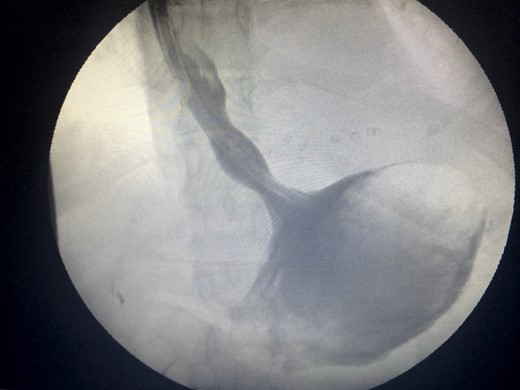

Two days prior to her admission, she had undergone upper gastrointestinal endoscopy for the same complaint in another center that revealed a dilated gastric lumen with herniation of the distal stomach, pylorus and first part of the duodenum into the left hemi-thorax (Fig. 2). She refused treatment and left against medical advice. She presented to our emergency department with worsening symptoms. Resuscitation was commenced with immediate nasogastric decompression, intravenous hydration and analgesia, proton-pump inhibitors and electrolyte replacement. A double contrast-enhanced computed tomography (CT) scan of the chest and the abdomen demonstrated a large diaphragmatic defect (7 × 7 cm) and a left diaphragmatic hernia containing a dilated stomach, suggestive of a gastric outlet obstruction (Fig. 3). A water-soluble gastrografin meal was performed, showing an intra-thoracic, mesentero-axial gastric volvulus (Fig. 4).

Flexible upper endoscopy showing herniation of the distal stomach, the pylorus and the first part of the duodenum into the left hemi-thorax.